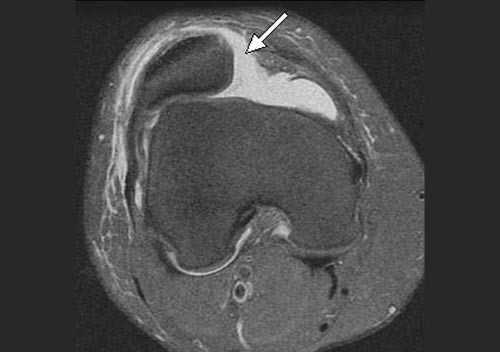

В большинстве случаев врач-травматолог легко диагностирует привычный вывих надколенника. Для этого проводится серия нагрузочных тестов, во время которых пациент демонстрирует страх получения повторного вывиха. Окончательный диагноз ставится после проведения магнитно-резонансной томографии (МРТ) коленного сустава. Как правило, исследование обнаруживает признаки повреждения медиальной пателло-феморальной связки, состояние подвывиха надколенника и признаки травматических повреждений хрящевого покрова.

Вне зависимости от выбора фиксирующих трансплантат фиксаторов (титановых, пластиковых, биорезорбируемых) в послеоперационном периоде требуется разгрузка сустава для создания условий биологической фиксации и перестройки трансплантата. Эти процессы, по данным МРТ исследований, занимают от 6 до 12 месяцев.